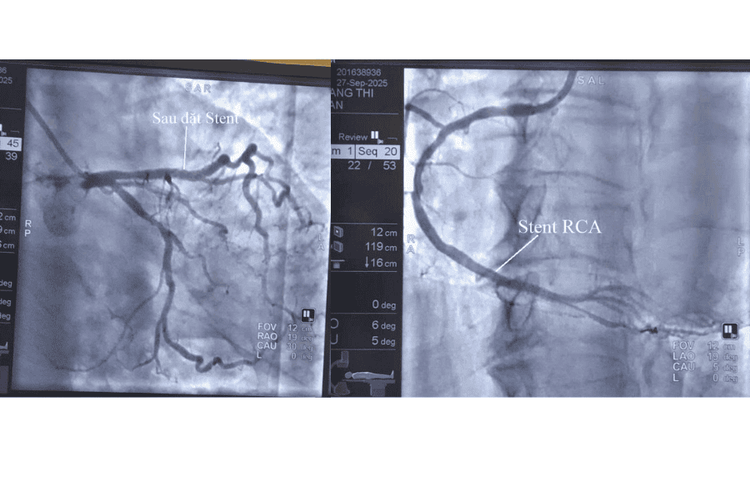

Đây là tình trạng tắc nghẽn nghiêm trọng, nếu không được tái thông kịp thời có thể gây ngừng tim, đột tử. Sau khi hội chẩn nhanh, các bác sĩ quyết định tiến hành đặt stent can thiệp để mở rộng các đoạn mạch bị hẹp nặng. Trong vòng 50 phút, ê-kíp đã đặt thành công 1 stent vào RCA và 1 stent vào LAD, tái thông mạch máu, đảm bảo dòng máu trở lại nuôi tim.